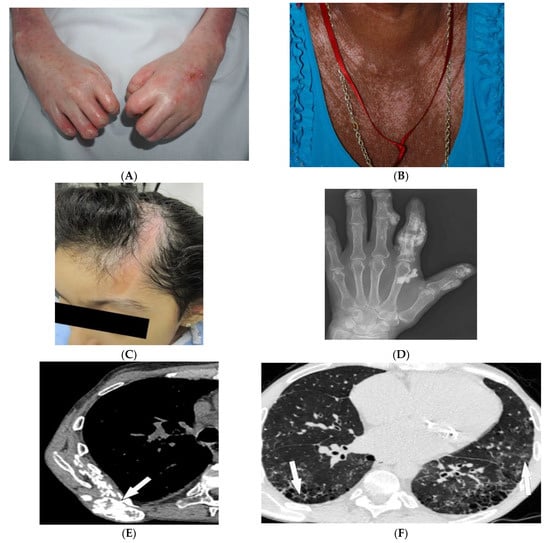

| Dermatomyositis | Atrophic dermal papules of dermatomyositis (Gottron papules), Gottron sign, heliotrope rash, V sign, shawl sign, calcinosis cutis Proximal nailfold erythema, capillary loop dilation and dropout, ragged cuticles Esophageal dysmotility Myositis ILD Malignancy | Calcinosis cutis Feathery edema-like SI of the muscles NSIP, OP, UIP |

| Sarcoidosis | Lupus pernio Erythema nodosum Lung nodules and adenopathy neurosarcoidosis Bone lesions | Reticulonodular lung opacities with upper lobe and peri-lymphatic distribution Leptomeningeal enhancement Lacy lytic bone lesions |

| Tuberous sclerosis complex | Facial angiofibroma Hypopigmented macules Shagreen patches Periungual fibromas Osseous abnormalities CNS hamartomas Renal AML Pulmonary LAM | Tubers, RMLs, SENs, SEGAs of brain Focal sclerotic bone lesions Hypertrophic osteoarthropathy Fat-containing renal mass Thin-walled lung cysts |

| Kaposi sarcoma | Erythematous or violaceous macules, plaques, nodules Pulmonary involvement Gastrointestinal involvement | Nodular enhancing masses Peribroncovascular nodules and halo sign |